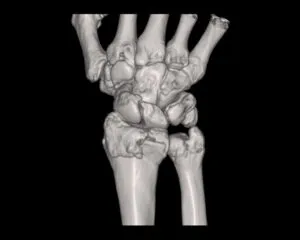

CT

GE社製Revolution ACT(16列)を導入しています。X線を利用して体の断面(輪切り)を撮像する検査です。この輪切りの画像をコンピューターで処理することにより、様々な方向からの断面像や3D画像を得ることができます。

CTで検査した画像